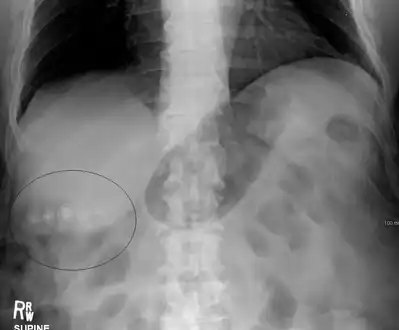

Gallstones as seen on plain X-ray